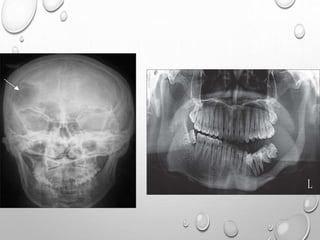

RADIOLOGY

HEAD

LARGE CRANIUM , THOUGH DECREASED AP DIAMETER –

BRACHYCEPHALY

NARROW FORAMEN MAGNUM

SHORT BASE OF SKULL

BASILAR IMPRESSION

FACE

FRONTAL BOSSING

DEPRESSED NASAL BRIDGE

NORMAL MANDIBLE ,SO IMPRESSION OF PROGNATHISM

• 1. DYSPLASTIC OR SQUARE

ILIAC BONES

2. NARROW SACRO-SCIATIC

NOTCHES

3. FLAT BILATERAL

ACETABULAR ROOFS

4. SHORT BOTH FEMORAL

NECKS

5. CHAMPAGNE GLASS-

SHAPED PELVIC CAVITY

DENTAL PANORAMIC RADIOLOGY IS EFFECTIVE IN

IDENTIFYING FEATURES PATHOGNOMONIC FOR

CLEIDOCRANIAL DYSPLADSIA.

SKULL

IN INFANCY DELAYED OR ABSENT OSSIFICATION OF CALVARIA

MULTIPLE WORMIAN BONES

WIDENING OF PRIMARY SUTURES – HOT CROSS BUN SIGN

SUPRAORBITAL , TEMPORAL SQUAMA , OCCIPITAL REGION ARE THICKENED

DEFORMED , ENLARGED FORAMEN MAGNUM

SMALL , UNDERDEVELOPED FACIALBONES

HYPOPLASTIC SINUS

NASAL BONE FAIL TO OSSIFY

SMALL MAXILLA , LARGE MANDIBLE

DELAYED , DEFECTIVE DENTITION